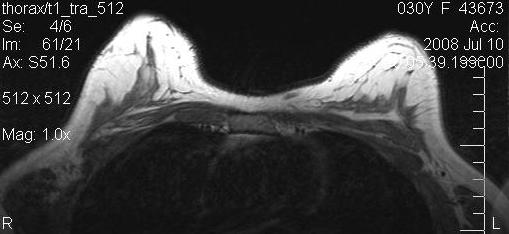

Magnetic resonance imaging (MRI) of the breasts was performed in 5 patients preoperatively and 6 months postoperatively. The evaluation by MRI based volumetry gave inconsistent results, presumably due to the fact that volume (the implant) is first removed, and then added by fat grafting in one procedure. Also, the form of the preoperatively often very tight breasts changed dramatically. All MRI showed massive increase in fat tissue. No cysts were observerd.

Figure 10 [Fig. 10] and Figure 11 [Fig. 11] show the MRIs of a patient pre- and postoperatively.

Figure 10: Preoperative MRI of a patient with capsular contracture

Figure 11: Postoperative MRI of the same patient after implant removal and subsequent fat grafting

The next two images show the preoperative and postoperative MRI scans of the patient of Figure 6 [Fig. 6] with capsular fibrosis after complete subpectoral placement (Figure 12 [Fig. 12], pre-op), and after implant removal and fat grafting (Figure 13 [Fig. 13], post-op). Remainders of the capsule are not to be seen after the procedure. The amount of fat grafted was only 2/3 of the implant volume. The patient was extremely pleased with the result and did not wish further volume increase.

Figure 12: Preoperative MRI of a patient with capsular fibrosis after complete subpectoral placement

Figure 13: Postoperative MRI of the same patient after implant removal and fat grafting. Remainders of capsule are not to be seen.